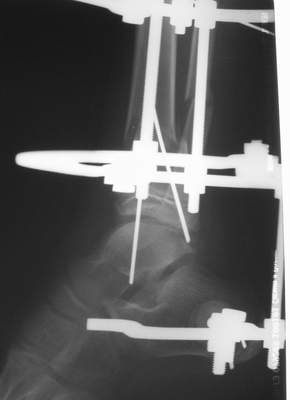

А аппаратами пользуетесь?

Нашел в комп-ре схожий случай:

1) з/репозиция, 2) фиксация 2 спицами, 3) аппарат, 4) фиксационные

спицы удалены...

См. аттачт.

А можно было наложить аппарат и по поводу ложного сустава...

По крайней мере не было бы укорочения (пусть и в 2 см)...